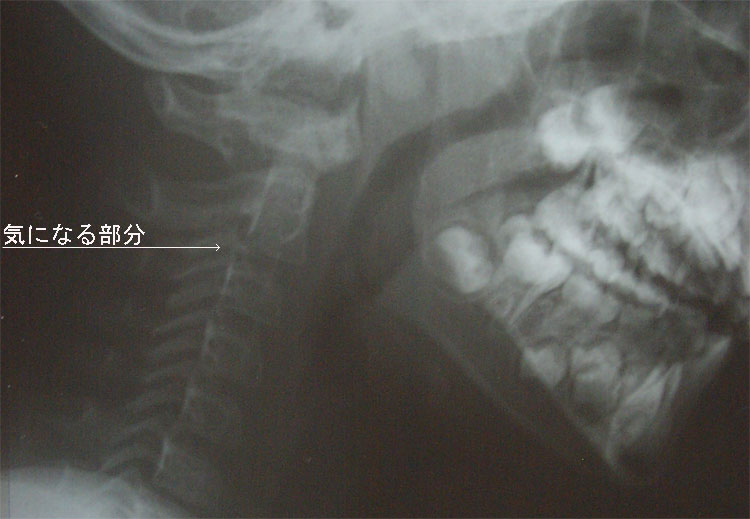

↓は、気になっている首のレントゲン写真です。 (次に生える歯で顎が大変な状態になってます)

↓は、気になっている首のレントゲン写真です。 (次に生える歯で顎が大変な状態になってます)